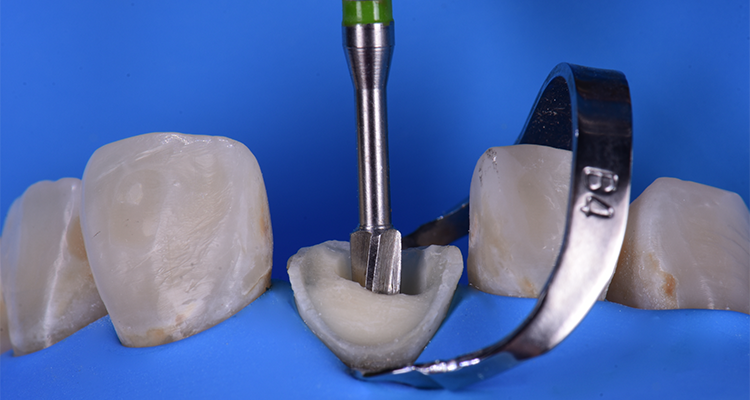

4 | Arco superior isolado de forma absoluta com auxílio do grampo B4, observando a pouca estrutura remanescente e consequentemente a necessidade de se utilizar pino de fibra de vidro.